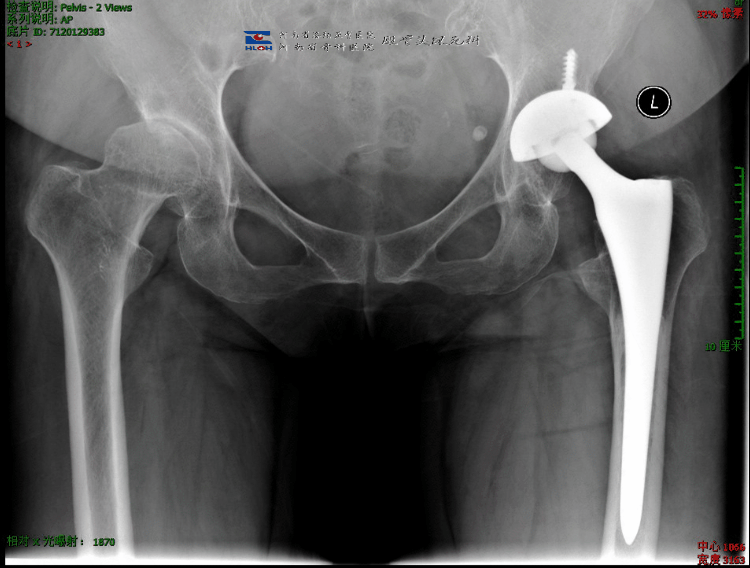

髋关节置换以后一般是这样的:

人工髋关节,分成两大部分:固定组件和摩擦界面

• 固定组件:髋臼杯①、股骨柄④,有时还会在臼杯上安装钉子以辅助固定;

• 磨损界面:髋臼内衬②、股骨头③,根据不同的配置,内衬可以是陶瓷材质,也可以是聚乙烯或高交联聚乙烯,股骨头可以是金属头或陶瓷头。

医生的重要性就体现出来了:为病人选择最合适的关节。否则,就会出现片子很美、病人很不爽的尴尬结果。如下面的案例1:

病人之前选用国产某小众品牌关节做了左侧置换,术后下肢变长,又因长时间卧床导致废用性骨质疏松,髋臼安装过高致旋转中心上移出现行走乏力、不协调,假体近端过宽、应力大导致大腿痛;我们采用了另一品牌的关节,根据对侧情况适当调整了肢体长度、旋转中心,使得双下肢能够在行走时协调一致,且选择了合适的假体,避免了股骨近端应力集中,术后第2天下地行走,避免了废用性骨质疏松;病人明显体验不一样的手术效果。